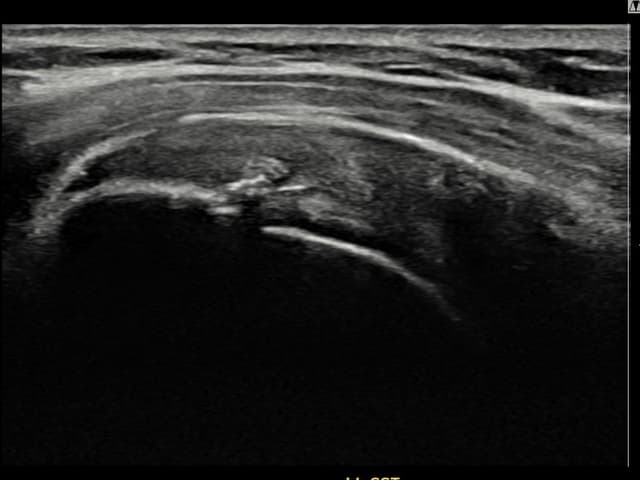

右侧 冈上肌腱 石灰化肌腱炎

13mm × 9mm